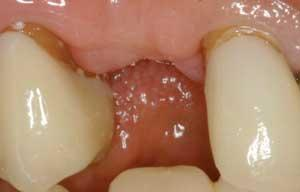

Figure 2 - Preop occlusal view. Adequate bone width did not necessitate ridge augmentation.